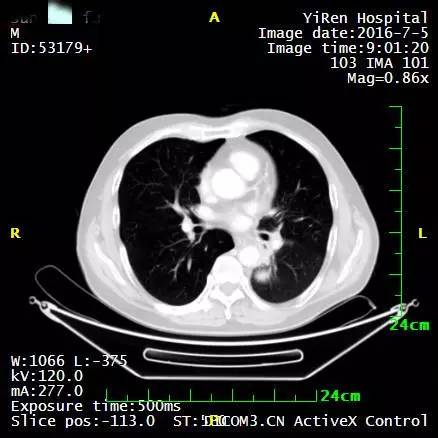

2016年4月,王先生接受了A45治疗,一个月后复查,病灶明显缩小,2016年7月复查,病灶进一步缩小,由于A45治疗具有明显的远观效应,能够激发自身的免疫系统,长期有效的消灭体内肿瘤,2016年12月,王先生肺部病灶几乎全部消失。

治疗后两个月

治疗后7个月

目前王先生状态良好,没有任何复发迹象。